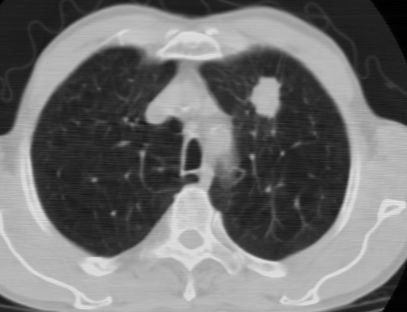

1、左肺上叶spn,毛刺+分叶+血管集束征,考虑周围型肺癌可能性大

2、全小叶性肺气肿。

1)左肺上叶周围型肺癌可能。2)两肺全小叶型肺气肿。

左上周围型肺癌,全小叶型肺气肿。